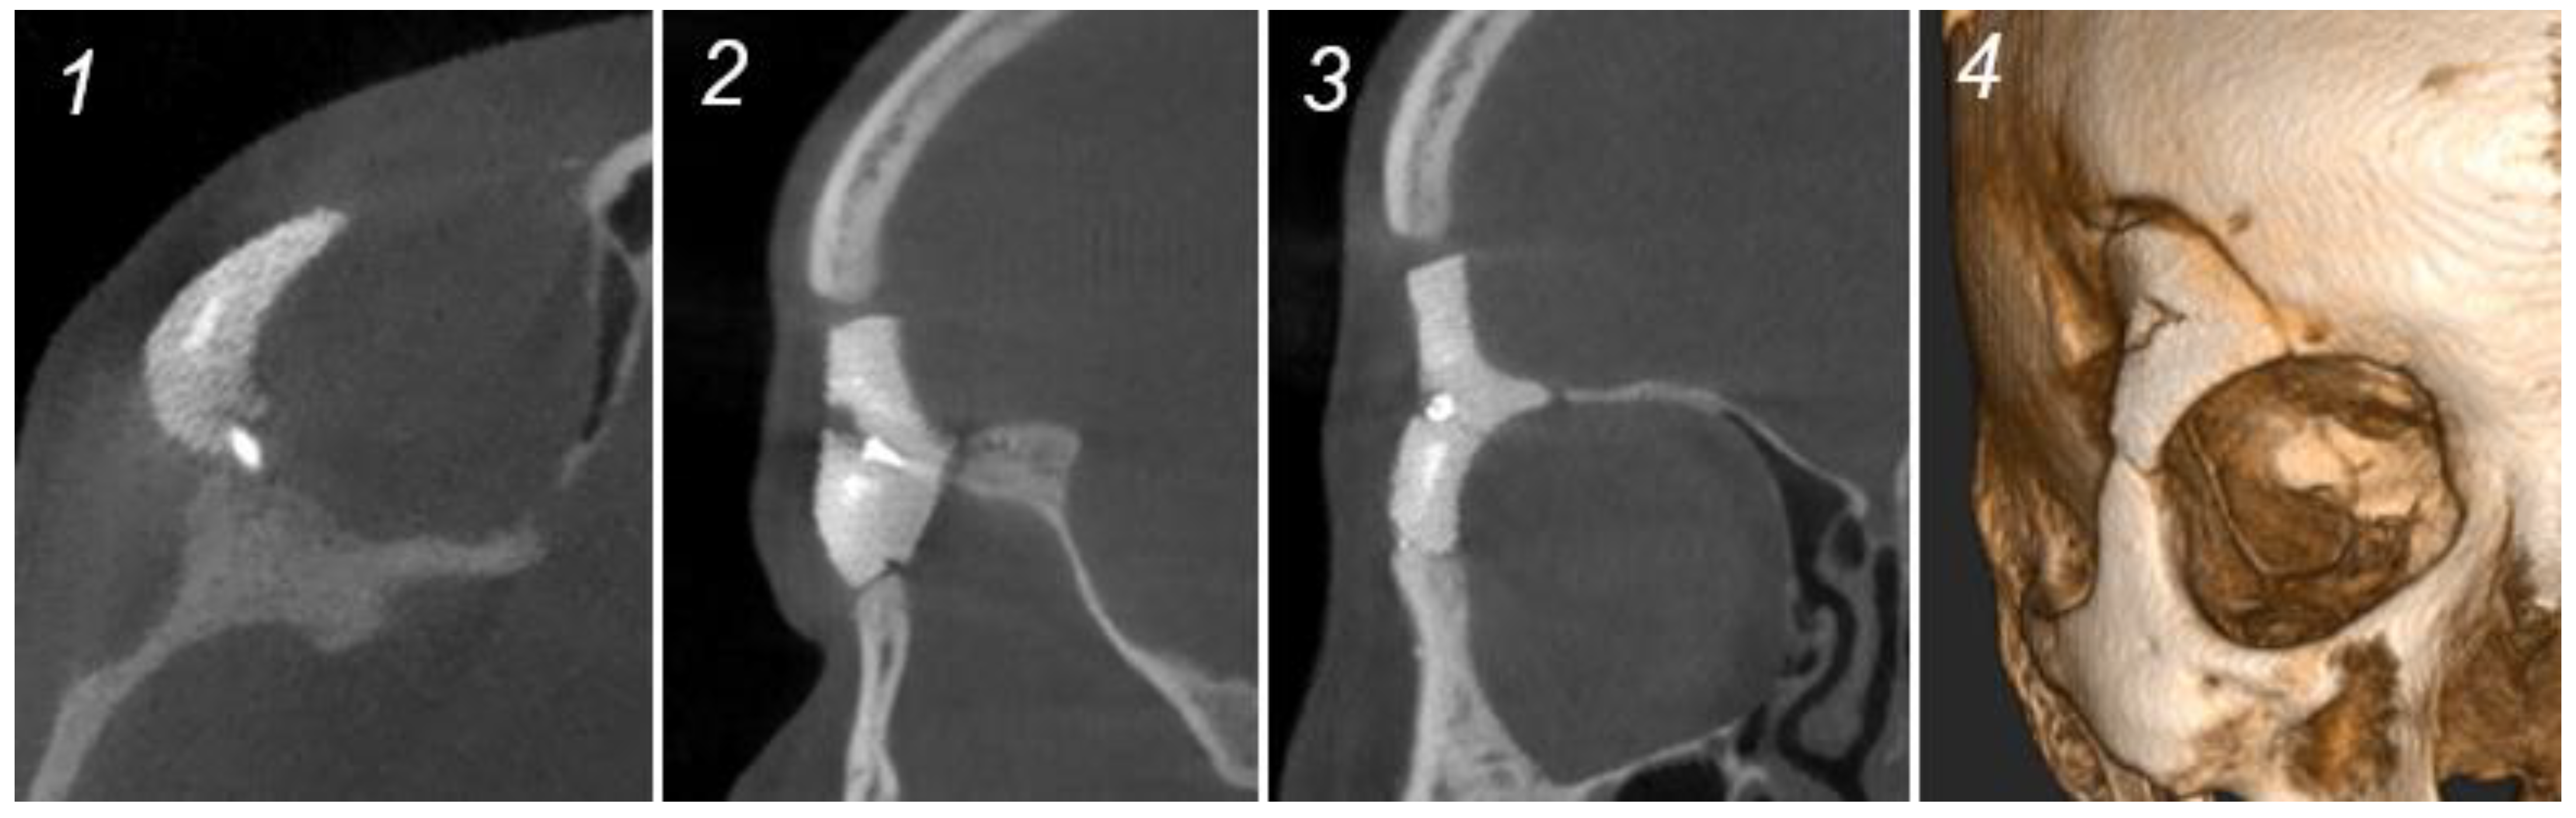

2.3. Intraosseous Hemangioma—Case 1

| Female | 42 | Intraosseous Hemangioma | Right supra-orbital rim | Hemicoronal | Supra-orbital and lateral orbital rim | None | Very good | 6 |